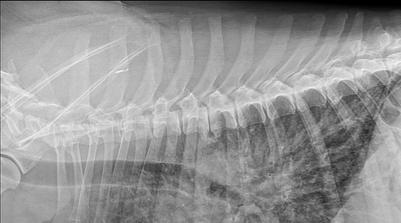

Blastomyces lives in the environment as a mold that produces fungal spores. When animals breathe in the spores, they are at risk for developing blastomycosis. After the spores enter the lungs, the body temperature allows the spores to transform into yeast. The yeast can stay in the lungs or spread through the bloodstream to other parts of the body, such as the skin, bones and joints, organs, and central nervous system (brain and spinal cord). It is always on the differential list in the hotbed regions in patients with pulmonary infiltrates or intra-thoracic lymphadenopathy.